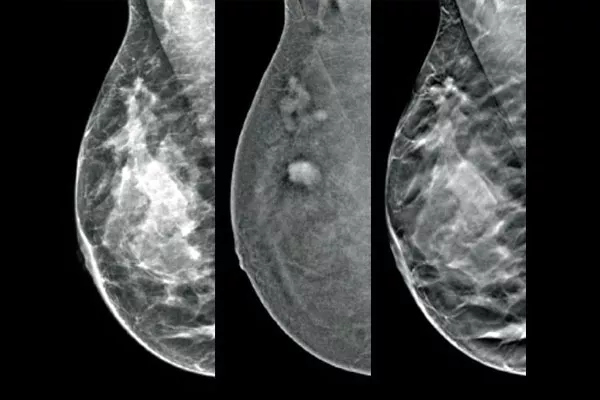

Target and biopsy lesions identified with 2D contrast-enhanced mammography through a stereotactic-based procedure, with a comparable diagnostic performance to a breast MRI procedure.1,2 Compare post-marker images in the same modality as the initial diagnostic contrast exam.

Affirm Contrast Biopsy software allows you to biopsy lesions identified during the I-View™ contrast-enhanced 2D mammogram. By leveraging the ability to provide 2D, contrast-enhanced, and tomosynthesis images under one compression,4 The Affirm Upright Breast Biopsy Guidance System enables a quick transition from screening to biopsy, leveraging the same proven imaging chain5 as the mammography system to improve 3D™ visualisation of suspicious lesions.**